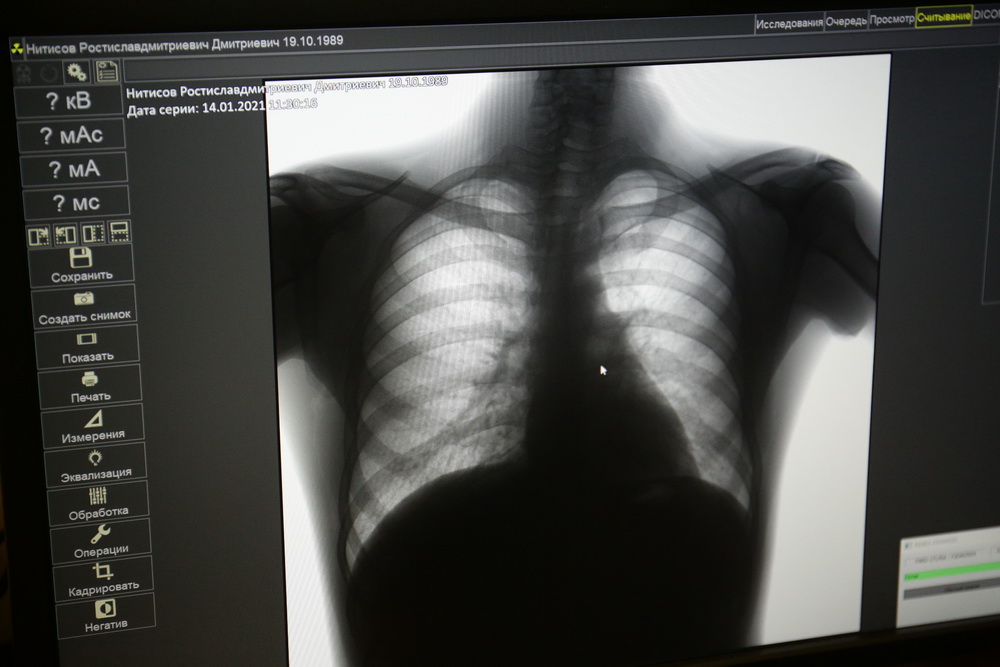

Новосибирцам предложили не отказываться от мониторинга здоровья из-за пандемии. Теперь на диспансеризацию можно записаться заранее: это позволяет избегать скопления людей. А новое оборудование улучшает качество исследований и сокращает время пребывания в поликлинике.

В 2020 году в поликлинике №27 диспансеризацию прошла только половина из запланированных пациентов. Из-за пандемии приёмы центров здоровья останавливали дважды. В этом году врачи работают быстрее — благодаря новому оборудованию. Маммоскан легко подстраивается под каждую пациентку — их теперь более 20 в день.

Фото: Ростислав Нетисов, nsknews.info (1-7, 9, 10), Алексей Танюшин (8)